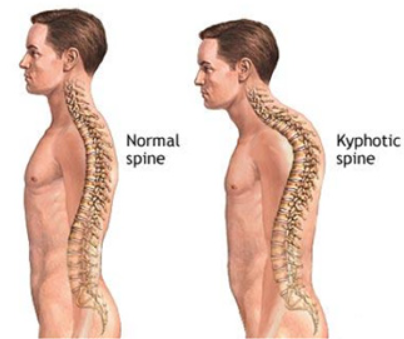

골격의 정렬 이상 또는 뼈의 외상

흉추가 과도하게 굽어있는 굽은등 상태인 후만상태(Excessive thoracic kyphosis)이거나 거북목(Increased cervical lordosis)인 경우에 견갑골문제가 발생할 수 있습니다.

후만과 거북목으로 인해 견갑골이 앞으로 빠지는 전인상태(Scapular protraction)이 되면서 견봉하공간이 좁아지면서 어깨 충돌가능성이 증가할 수 있습니다.

굽은등, 거북목 -> 견갑골 전인상태 -> 견봉하공간 좁아짐 -> 충돌 증가

환자의 경부, 흉부의 해부학적 자세 시 흉추의 Kyphosis, 경추의 거북목, 측만, 견갑골의 대칭성 확인

흉추의 과후만을 교정해주는것이 재활초기에 매우 중요합니다. 여러가지 스트레칭도 중요하지만 평소 바른자세도 지속적으로 시행해주어야합니다.